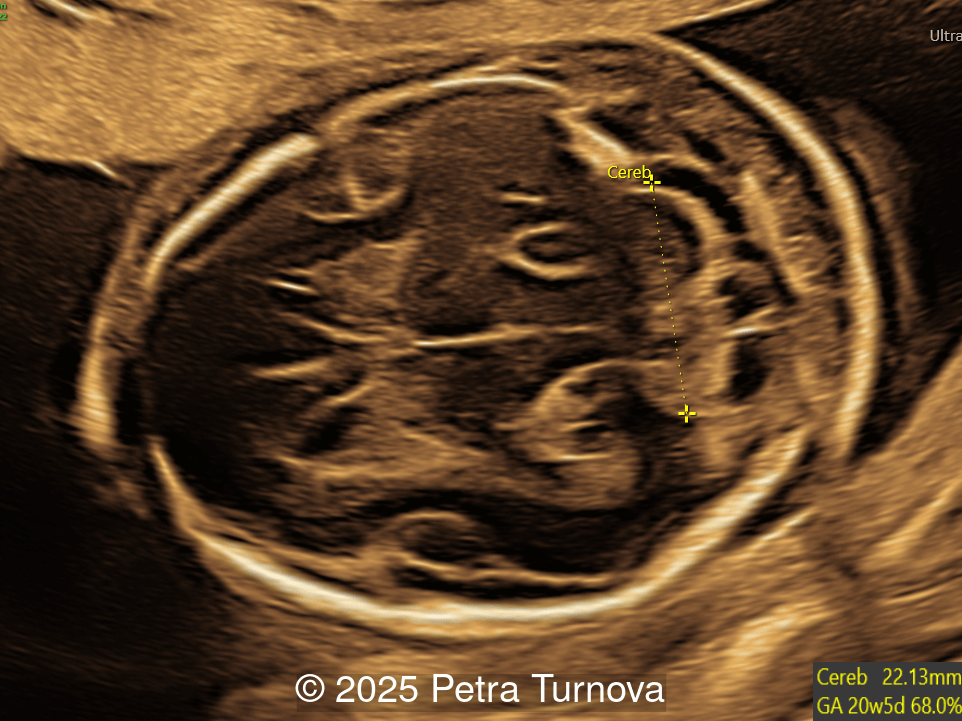

A woman with no significant medical history presented to our center at 20 weeks and 5 days for fetal anatomic survey. The following findings were observed:

Image 2

Our imaging revealed malformations in all four limbs with elbow, wrist, and knee joints fixed in extension, as well as foot and ankle malformations. Profile abnormalities were observed with prefrontal edema, flat profile and retro-micrognathia. Ultrasound demonstrated minimal stomach filling related to a lack of swallowing ability and hypoplastic lungs due to poor diaphragmatic movement. Nuchal edema was present.